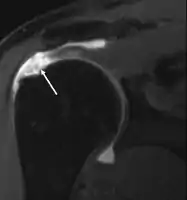

MRI

Magnetic resonance imaging (MRI) and ultrasound[46] are comparable in efficacy and helpful in diagnosis, although both have a false positive rate of 15–20%.[47] MRI can reliably detect most full-thickness tears, although very small pinpoint tears may be missed. In such situations, an MRI combined with an injection of contrast material, an MR-arthrogram, may help to confirm the diagnosis. It should be realized that a normal MRI cannot fully rule out a small tear (a false negative) while partial-thickness tears are not as reliably detected.[48] While MRI is sensitive in identifying tendon degeneration (tendinopathy), it may not reliably distinguish between a degenerative tendon and a partially torn tendon. Again, magnetic resonance arthrography can improve the differentiation.[48] An overall sensitivity of 91% (9% false negative rate) has been reported, indicating that magnetic resonance arthrography is reliable in the detection of partial-thickness rotator cuff tears.[48] However, its routine use is not advised, since it involves entering the joint with a needle, with the potential risk of infection. Consequently, the test is reserved for cases in which the diagnosis remains unclear.

Diagnostic modalities, dependent on circumstances, include X-ray, MRI, MR arthrography, double-contrast arthrography, and ultrasound. Although MR arthrography is currently considered the gold standard, ultrasound may be most cost-effective.[34] Usually, a tear will be undetected by X-ray, although bone spurs, which can impinge upon the rotator cuff tendons, may be visible.[35] Such spurs suggest chronic severe rotator cuff disease. Double-contrast arthrography involves injecting contrast dye into the shoulder joint to detect leakage out of the injured rotator cuff,[36] and its value is influenced by the experience of the operator. The most common diagnostic tool is magnetic resonance imaging (MRI), which can sometimes indicate the size of the tear, as well as its location within the tendon. Furthermore, MRI enables the detection or exclusion of complete rotator cuff tears with reasonable accuracy and is also suitable for diagnosing other pathologies of the shoulder joint.[37]

Ultrasound

Musculoskeletal ultrasound has been advocated by experienced practitioners, avoiding the radiation of X-ray and the expense of MRI while demonstrating comparable accuracy to MRI for identifying and measuring the size of full-thickness and partial-thickness rotator cuff tears.[49] This modality can also reveal the presence of other conditions that may mimic rotator cuff tear at clinical examination, including tendinosis, calcific tendinitis, subacromial subdeltoid bursitis, greater tuberosity fracture, and adhesive capsulitis.[50] However, MRI provides more information about adjacent structures in the shoulder, such as the capsule, glenoid labrum muscles, and bone, and these factors should be considered in each case when selecting the appropriate study.